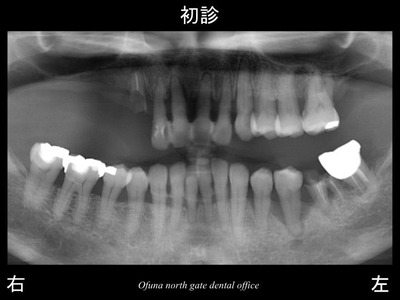

初診のレントゲンから見てみましょう!

問題点を順番に説明します。

上顎右側の奥歯が欠損しています。

前歯の右側は折れており、歯の根のみが残っている状態です。

上顎の前歯部はグラグラで指で触っても取れそうな状態です。

下顎前歯部もグラグラです。

下顎左側の奥歯もグラグラの歯が存在していますし、

折れている歯も存在します。

これでは、食事も十分できない状態です。

歯周病が進行していることもあり、

多くの部位で 歯肉が腫れ、出血も認められます。

重度歯周病であり、典型的な総入れ歯に向かっている状態と言えます。